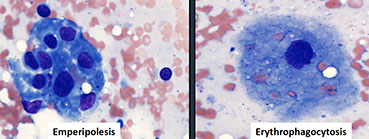

Micro: dilated sinuses c lymphs, plasma cells, and foamy histiocytoid cells c vesicular nuclei and lots of pale cytoplasm

- histiocytes have emperipolesis / lymphocytophagocytosis (they ate some lymphs)

•Histiocytes: large with abundant pale cytoplasm showing emperipolesis.

•Positive: S100, histiocytic markers (CD68, CD163, CD4, CD11c, CD33, fascin), Cyclin D1 (often aberrantly expressed in the nuclei of clonal / neoplastic histiocytic proliferations), OCT2

•Negative: CD1a, CD207 (Langerin), BRAF V600E.

Touch prep from patient with Rosai Dorfman, histiocyte with abundant eosinophilic cytoplasm with ingested matieral. Cell was CD14+, CD68+, S100+, and CD1a- [6]